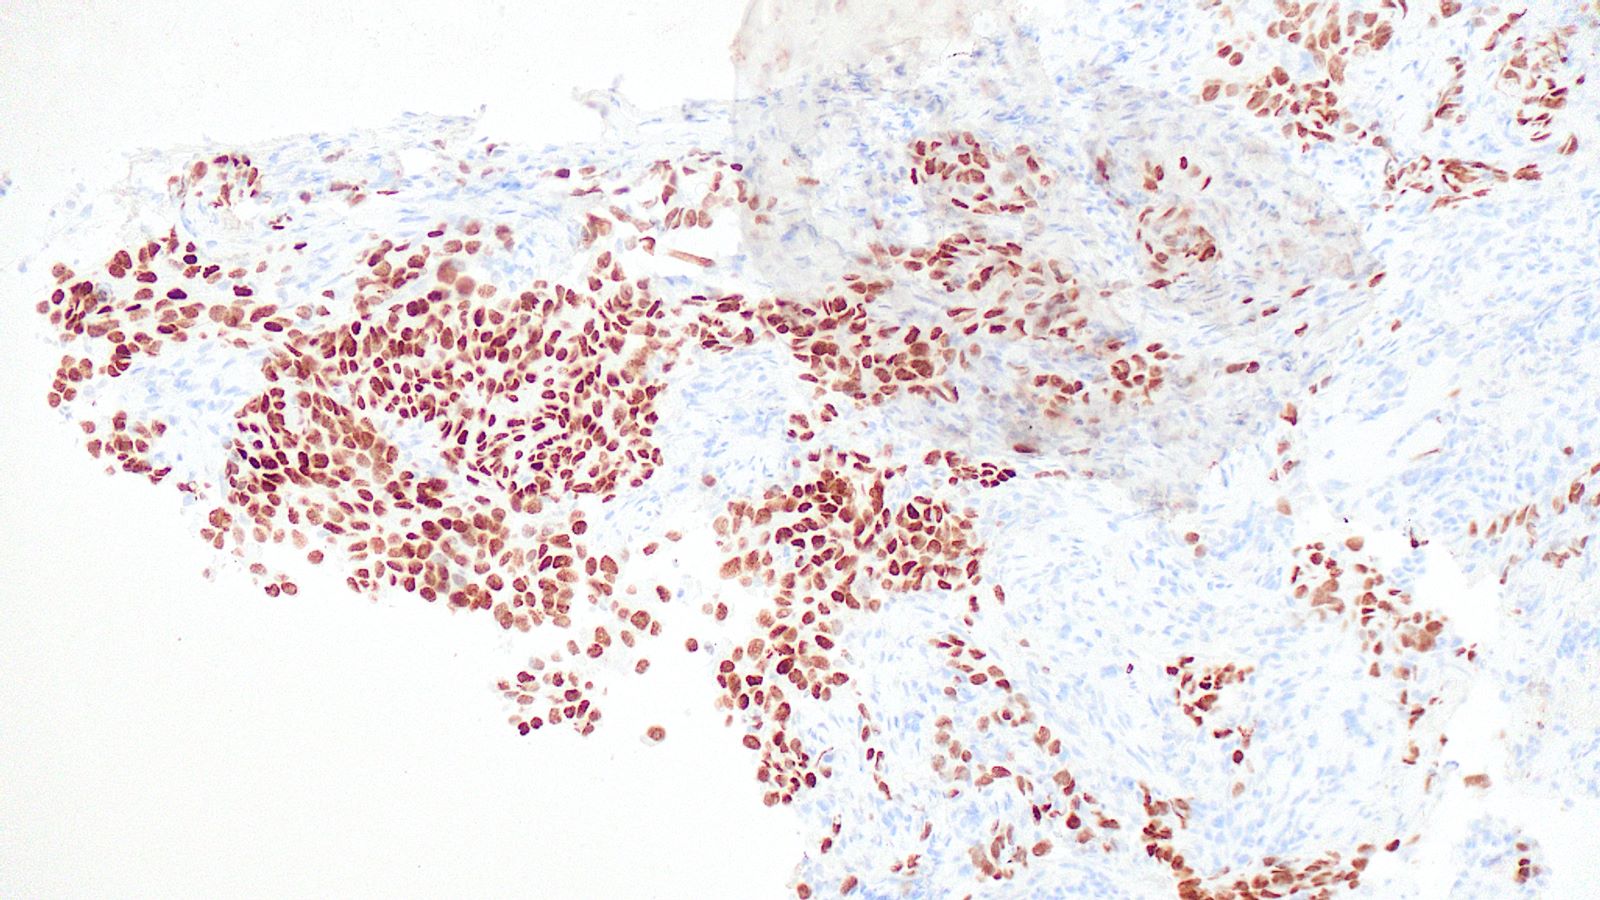

Board review style question #3

A 75 year old man with a 100 pack year smoking history presents with hemoptysis and is found to have a hilar mass and lymphadenopathy. Biopsy of one of the lymph nodes reveals the proliferation seen in the above images. Mitotic activity is approximately 35 mitoses per 2 mm2 and necrosis is present. Immunophenotyping is attempted; however, the block was inadvertently exhausted and stains are not available. What is the best diagnosis that can be rendered?

Board review style answer #3

E. Small cell carcinoma. Small cell carcinoma remains a morphologic diagnosis and does not require immunophenotyping for confirmation. The clinical history and description of the malignant cells are consistent with a diagnosis of small cell carcinoma. Immunophenotyping, including the use of Ki67, is most useful in cases with more ambiguous morphologic features or in crushed biopsies where morphologic features are obscured.